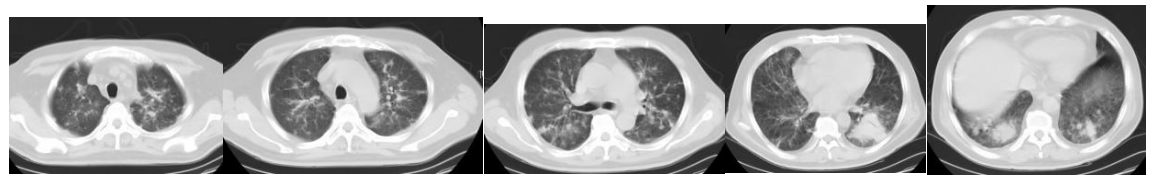

CT(2023-05-22):双肺存在散在的渗出病变,见图1。

图1. 入院前胸部CT(2023-05-22)